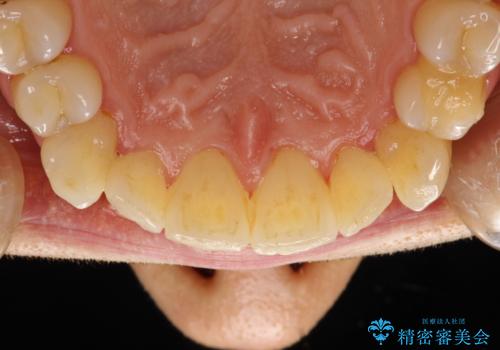

歯磨き中に血が出る PMTCで歯石除去

- 毎日の歯磨きの際に出血する。歯科でにクリーニンングをしばらくしていないとのことでした。PMTC60分コースを行いました。